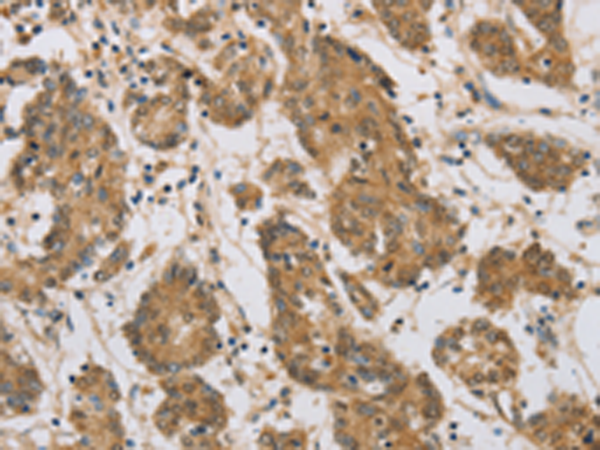

分类: 科研抗体货号: P08198别名: CTX; CP27; CYP27应用: WB,IHC反应种属: Human, Mouse